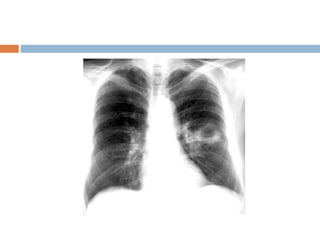

How to read a normal CXR

 This is chest radigraph , PA view with normal

exposure , no rotation and without any

apparent bony abnormality . Trachea is placed

centrally and lung fields are clear with normal

broncho- vescicular markings . Cardivascular

silhoutte is within normal limits with normal

cardiothoracic ratio. Mediastinum, costo

phrenic , cardio phrenic angles , dome of

diaphragm and soft tissue shadow within

normal limits .

How to reada normal CXR  This is chest radigraph , PA view with normal exposure , no rotation and without any apparent bony abnormality . Trachea is placed centrally and lung fields are clear with normal broncho- vescicular markings . Cardivascular silhoutte is within normal limits with normal cardiothoracic ratio. Mediastinum, costo phrenic , cardio phrenic angles , dome of diaphragm and soft tissue shadow within normal limits .